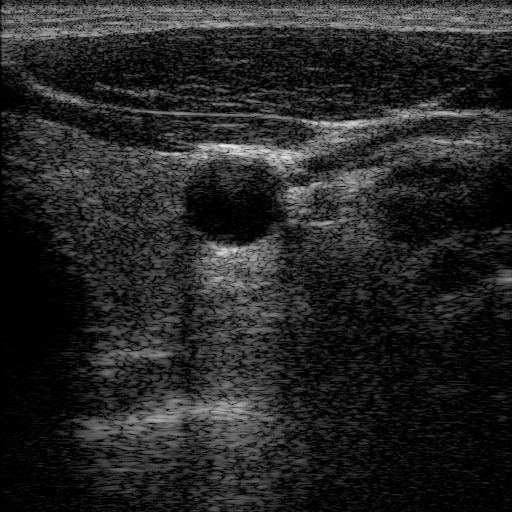

Speckle noise in US is highly tissue-dependent and inherently approximately multiplicative, meaning that its intensity can vary significantly—often with fluctuations comparable to those of the tissue signal itself [57, 76]. In addition, unlike pixel-wise Gaussian noise, speckle noise typically appears in clusters, and the grainy pattern varies in intensity across different tissues, which blend with image features (see Fig. 2). These characteristics make it challenging to remove speckle while preserving essential tissue features.

This implies that the statistical behaviour of speckle in B-mode images fundamentally differs from the independent noise assumptions commonly made in self-supervised denoising methods [49, 43, 32]. Unlike pixel-wise random noise (e.g., Gaussian, Poisson, or Salt-and-Pepper), speckle exhibits strong local spatial dependencies and large-scale granular patterns, making it substantially more difficult to model and suppress. Although it may appear visually similar to noise, speckle originates from the coherent interference of echoes scattered by sub-wavelength tissue structures, and is therefore not truly random. As noted in [18, 64], speckle does not qualify as “noise” in the conventional sense used in natural image or CT/MRI processing. Nonetheless, for consistency and ease of understanding, we use the terms “speckle” and “noise”, as well as “despeckling” and “denoising”, interchangeably throughout this paper, while fully acknowledging their fundamental differences.

An intuitive comparison between US speckle and common pixel-wise noise types is shown in Fig. 2. It can be seen that tissue-dependent speckle causes more severe degradation than other noise types. Moreover, degraded examples from the BSD68 dataset [56] illustrate that the detail loss induced by US speckle and related artefacts is nearly irreversible. This highlights the challenge of speckle reduction, as speckle is closely linked to the underlying tissue’s texture and structure.